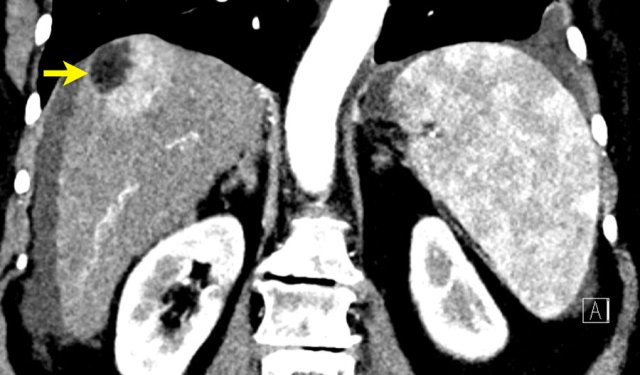

The coronal images shows a large lesion treated with TACE with residual areas of mild arterial enhancement and washout due to untreated supply via a phrenic artery (yellow arrow): LRTR-viable.

Continue with the axial image ...

Note there is irregularity of the peritoneal fat anteriorly due to capsular rupture (arrow).